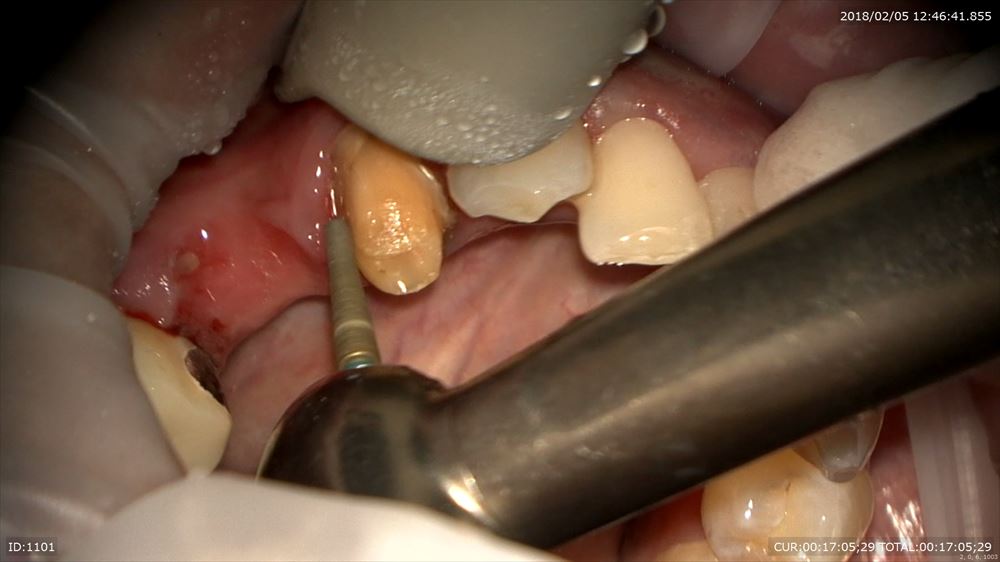

ブリッジを外して仮歯へ

外して

仮歯作成

手間をかけて

セット